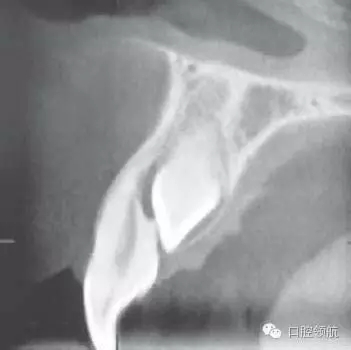

圖2.40所示什么?

拍攝了錐形束CT(CBCT),用于觀察UR1牙根的情況。證實(shí)UR1牙根的吸收。